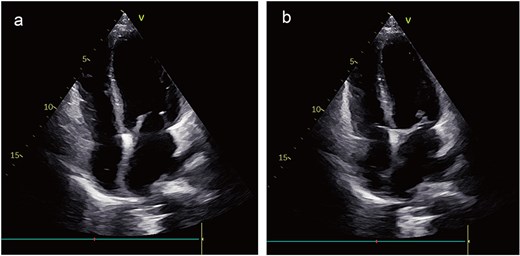

A 41-year-old female was admitted to our hospital with chest tightness and dyspnea for the past 2 weeks. Physical examination revealed bilateral lower limb edema without cardiac murmurs or jugular venous distention. Laboratory findings were notable for hypoalbuminemia (30 g/L) and an elevated D-dimer level (6.99 mg/mL), without remarkable blood routine examination and serum chemistry. Electrocardiography demonstrated sinus tachycardia and low-voltage complexes (Fig. 1). Echocardiography identified a large, well-demarcated hypoechoic mass (82 × 54 × 58 mm), nearly occupying the entire right atrial cavity (Fig. 2a and b). Contrast-enhanced computed tomography confirmed right pleural effusion and a right atrial occupying lesion (Fig. c and d). Subsequent right thoracentesis revealed exudative fluid with no evidence of malignancy on cytological examination. Further metabolic imaging with PET-CT (Fig. 3a and b) and PET-MR (Fig. 3c and d) demonstrated a hypermetabolic soft tissue mass within the right atrium, highly suggestive of primary cardiac angiosarcoma, with no signs of distant metastasis.

Preoperative imaging. Echocardiography identified a large mass, nearly occupying the entire right atrial cavity (a) and (b). Contrast-enhanced computed tomography showed a right pleural effusion and a right atrial occupying lesion (c) and (d).

During surveillance at 3 years postoperatively, echocardiography showed no local recurrence; however, chest CT identified multiple pulmonary nodules suggestive of metastatic disease. Genetic profiling demonstrated PD-L1 positivity, prompting initiation of immunotherapy with tislelizumab. At the 4-year follow-up, the patient remained clinically stable with no echocardiographic evidence of local recurrence (Fig. 6a and b) and continues under close monitoring.

Postoperative images. The echocardiogram indicated no signs of local recurrence (a) and (b).